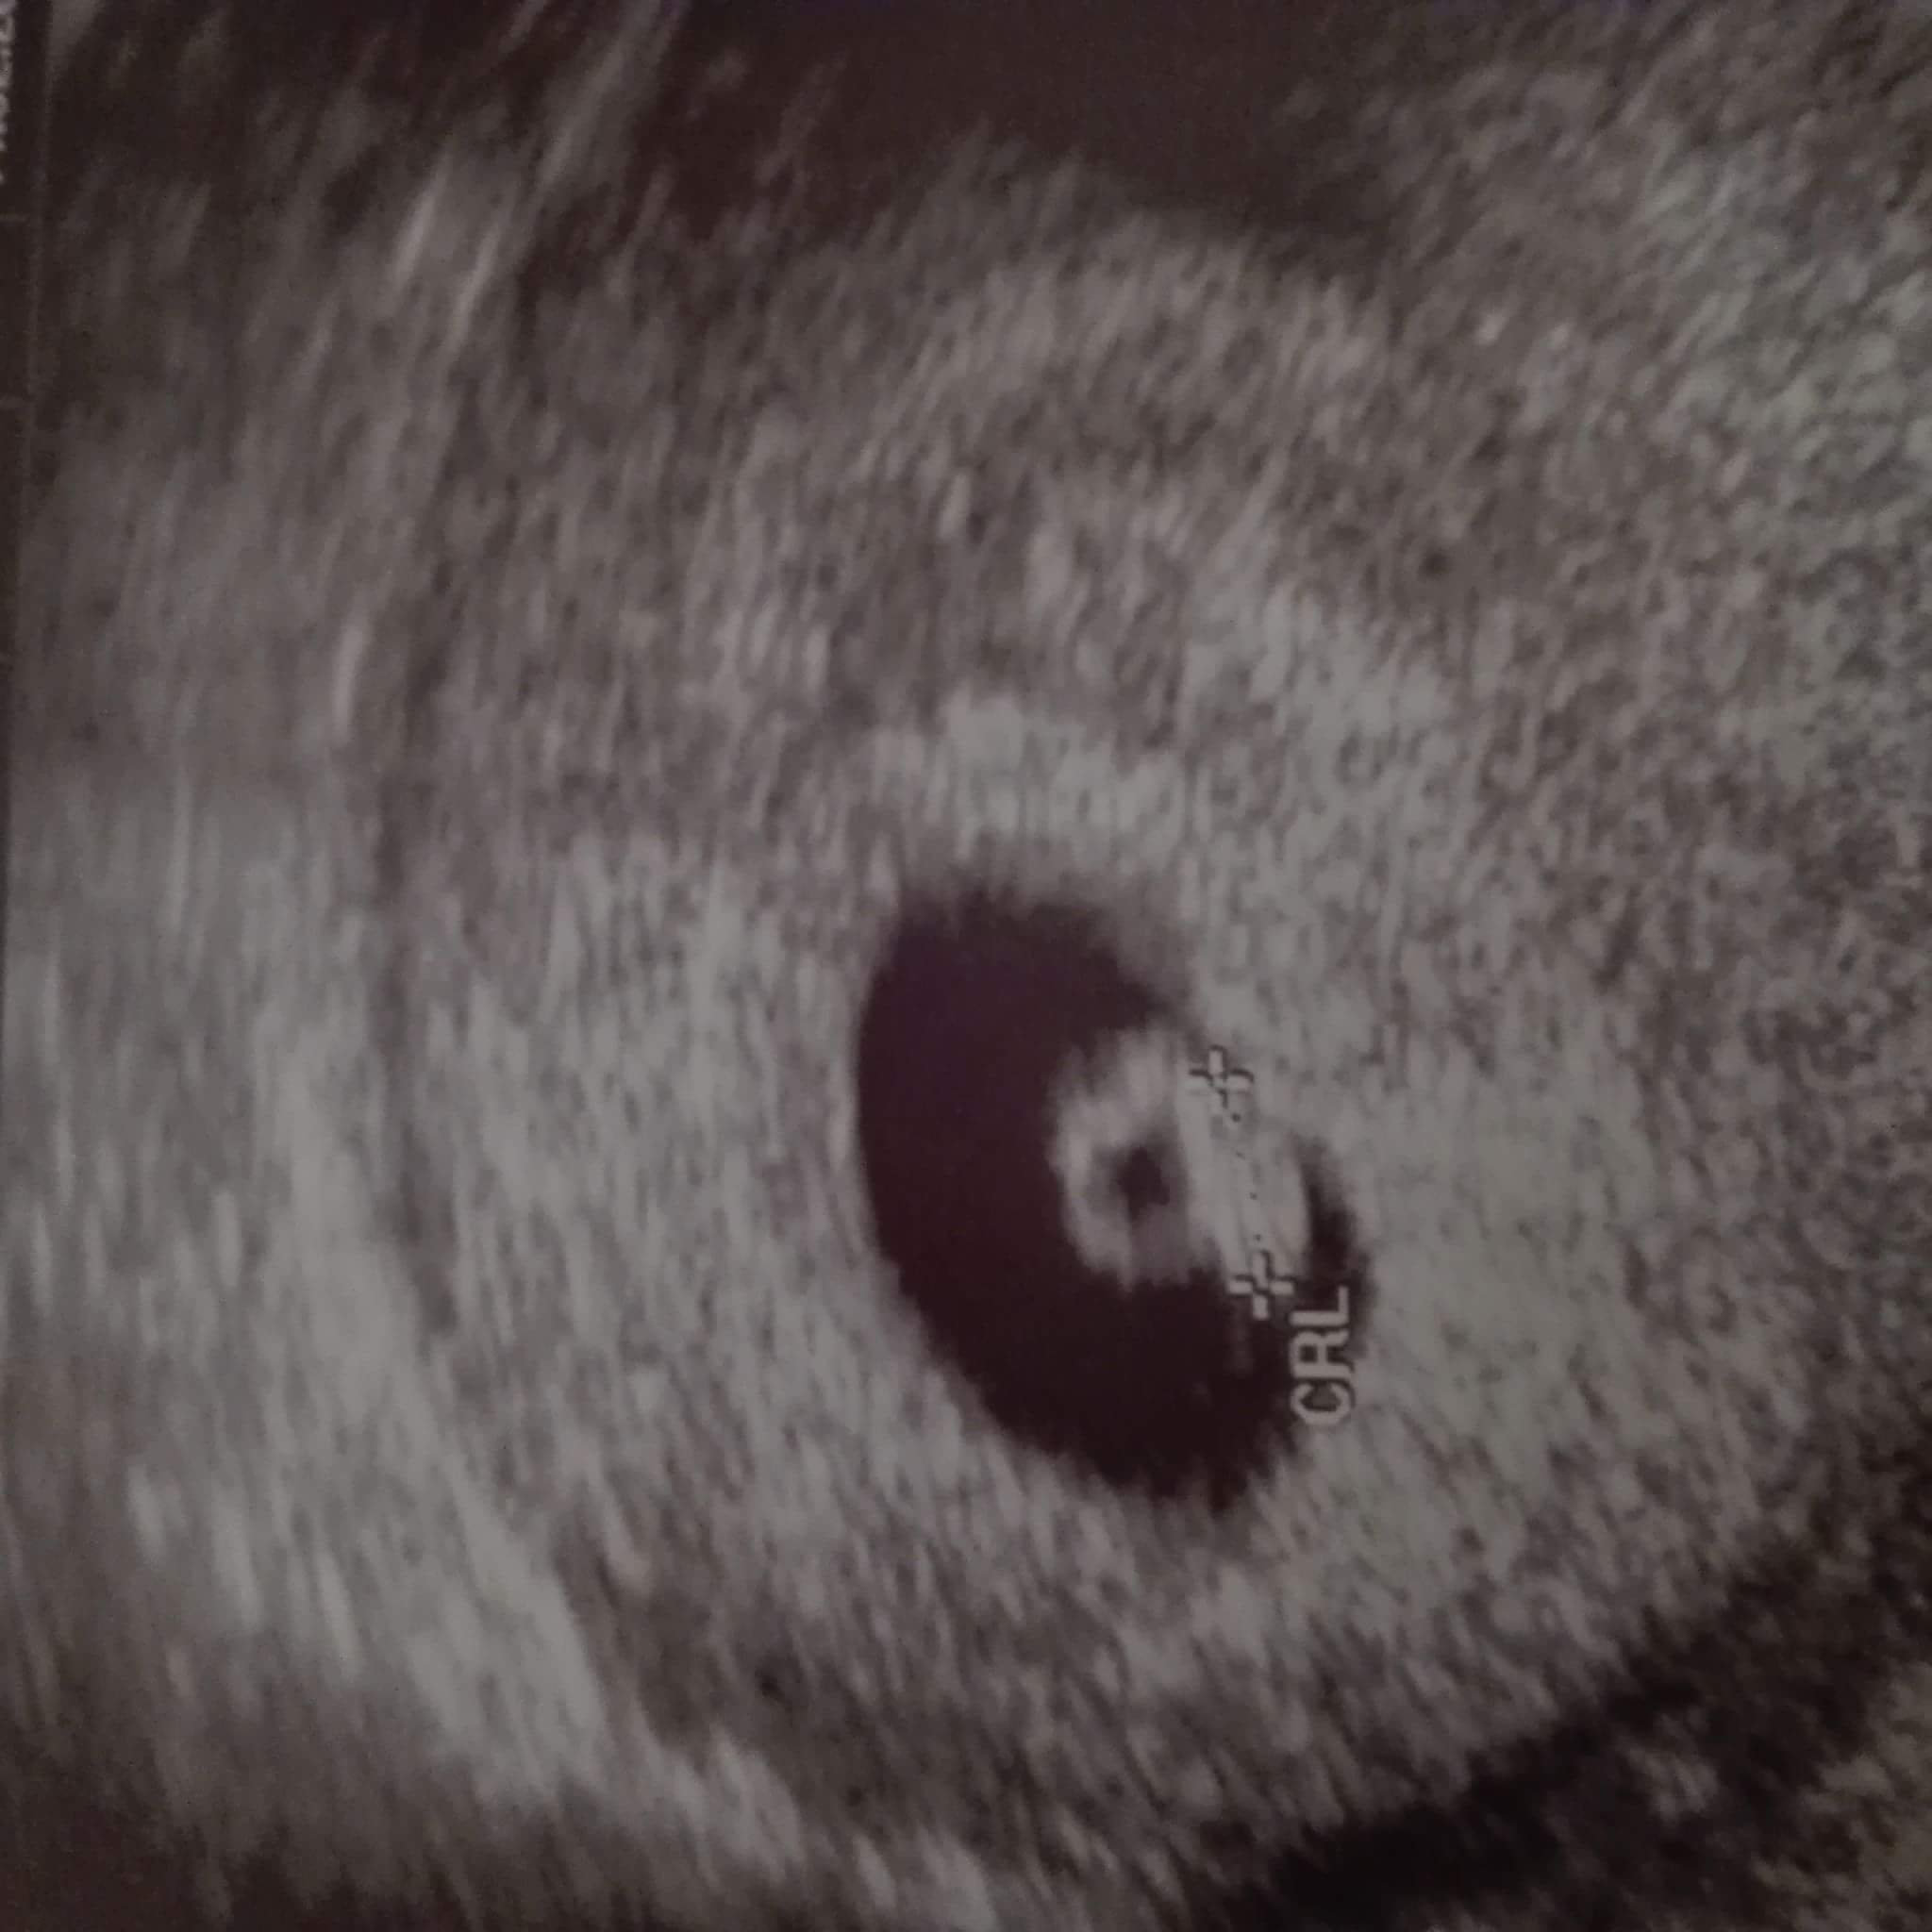

Zarodeczek ok. 5 mm z akcja serduszka :) pikalo jak szalone. Za 3 tyg wizyta i wtedy wstawię foto :) jak bedzie juz duza kluseczka :)

Jestem taka szczęśliwa :)